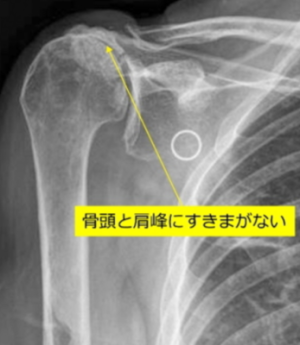

Preoperative X-ray (X-ray of cuff tear arthropathy)

Please refer to the illustration of cuff tear arthropathy. The space between the humeral head and the acromion is absent compared to normal.